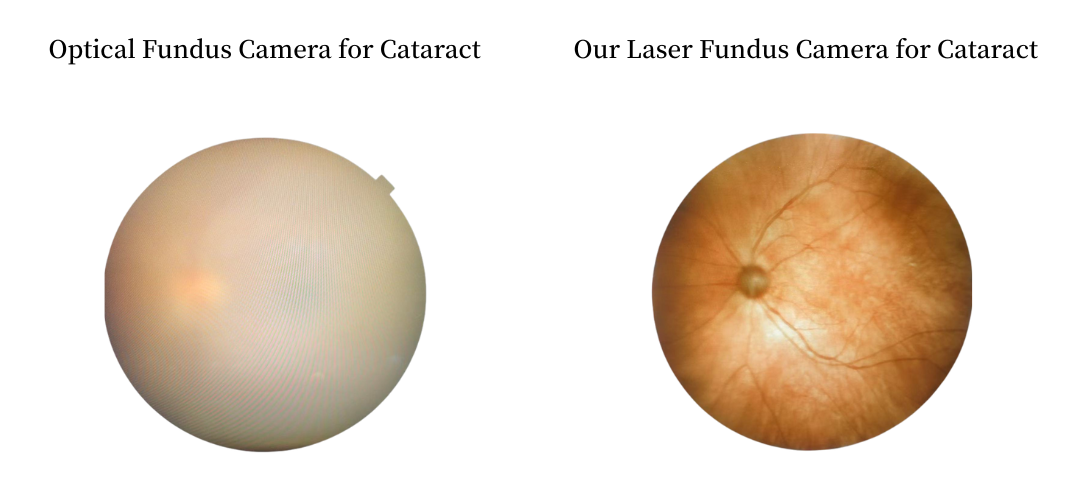

Retina Examination Under Cataracts

Examining fundus diseases through cataracts is a crucial topic in ophthalmology. Traditional fundus cameras cannot see through cataracts to capture fundus conditions. However, our DF600 scanning laser ophthalmoscope can penetrate moderate cataracts, providing a glimpse into the fundus and offering greater convenience for fundus examinations in patients with cataracts.